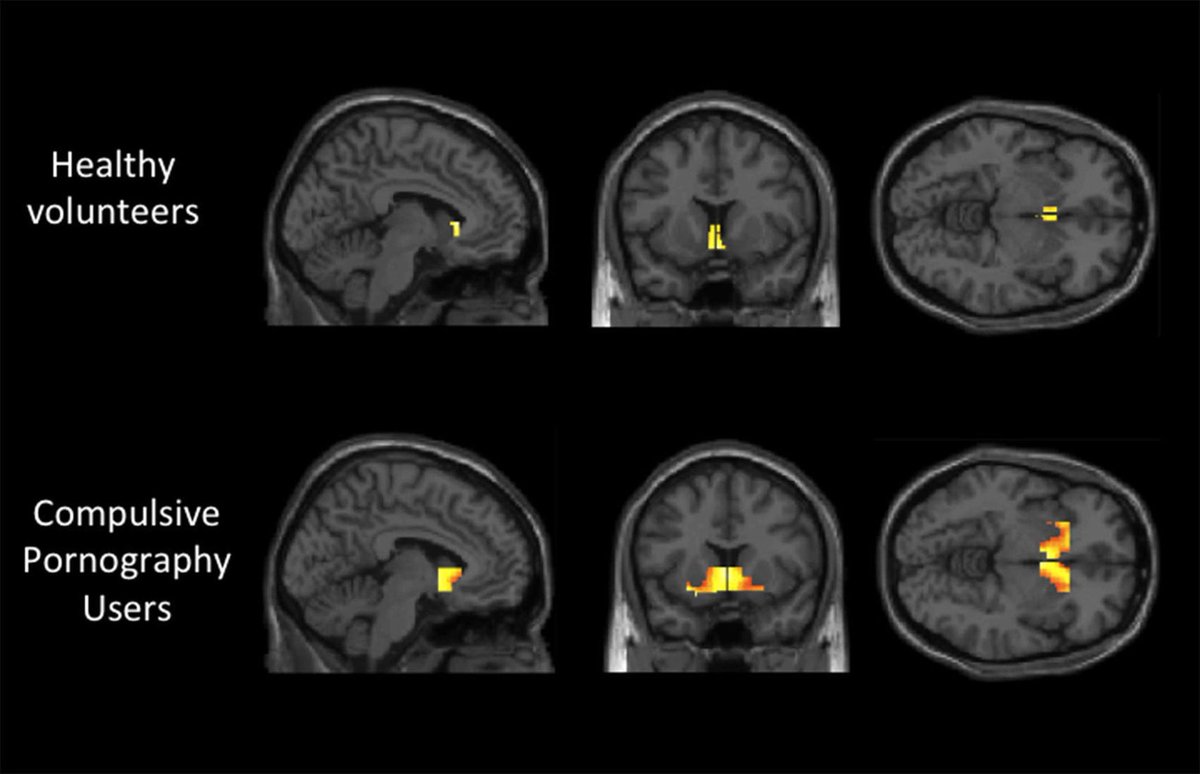

مشاهدة الأفلام الإباحية تشبه تعاطي الهيروين .

عندما تشاهد المواد الإباحية، يتم تعطيل القشرة الأمامية للدماغ.

الإباحية تدمر الدماغ.